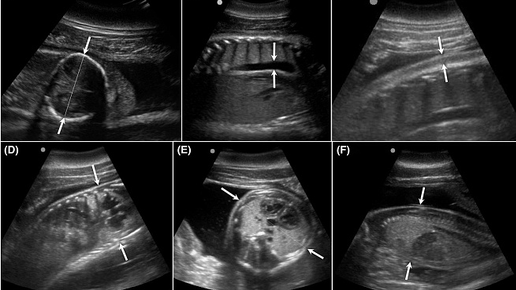

Впервые получены УЗИ-снимки беременной самки дельфина. Они одновременно прекрасны и трагичны

Плавание в загрязненных нефтепродуктами водах отрицательно сказывается на здоровье дельфинов, а если животное при этом беременно, последствия могут быть ужасными. В результате взрыва на нефтяной платформе Deepwater Horizon и последующего разлива нефти в 2011 году резко сократилось количество положительно завершившихся беременностей у дельфинов-афалин, обитающих в Мексиканском заливе. Основными причинами стали гибель эмбрионов, стресс и пневмония матери – все это тесно связано с загрязнением воды нефтепродуктами...